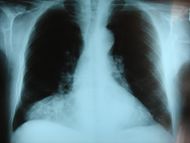

| Frontal chest X-ray showing a hernia of Morgagni | |